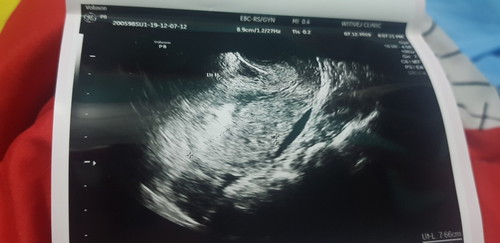

ตอน 5 วีคก็เจอแต่ถุงค่า ซาวจากท้องนะคะ หมอเลยให้มาอีกทีต้อง 9 วีคค่า น้องโตขึ้น อาจจะเป็นเพราะตอน 5 วีค น้องยังเล็กไป -รูปนี้ คุณหมอซาวให้ตอน 9 วีคค่า-